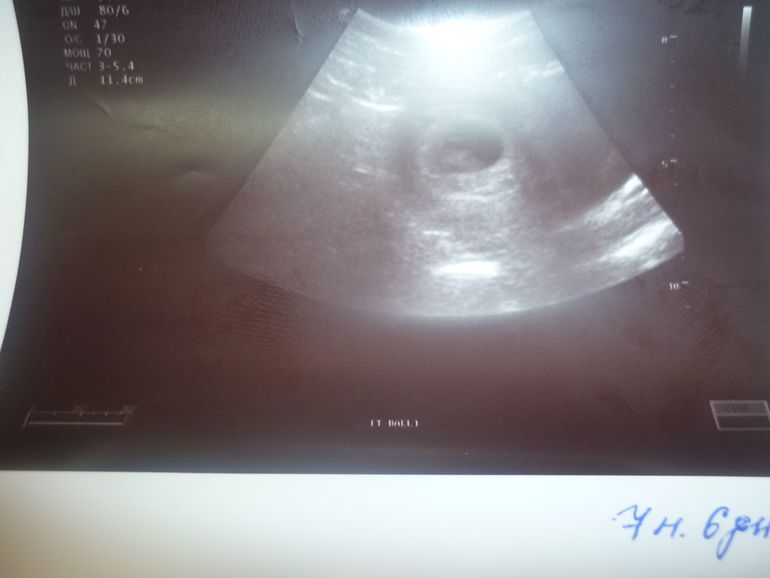

УЗИ, КТГ, доплерДевочки привет всем мои дорогие !!!!! сегодня меня тряхонуло сходить на узи ..............и я пошла ...результат его под катом узистка такая эмоциональная прям вся сияла от счастья .....повернула мне монитор и говорит смотри.........я прослезилась как дура .........смотрю и вижу свою малявку .она попросила притихнуть и дать мне послушать сердцебиение ..там слезы еще больше ...говорит вот вот ваше сердечко нормальное четерыхкамерное ......отлично бьется ......наш ростик целых 13 мм.........и желтый мешок есть.....размеры она особо не смотрела т.к я ж для себя и не планово ......и тут она говорит смотри смотри как он отворачивается от меня ........там так интересно ....в голое и мысли и слезы и хотелось на ее местев кресле посидеть ане задирать головушку( хоть и так она по максимому мне развернула монитор) и потом пауза она говорит подожди я слышу еще одно ....или мне показалось.ну поводила поводила и говорит всетаки мешочек это ......в общем вся в эмоциях положительных .....аааааааааа какое счастье

...ну и наше первое фото